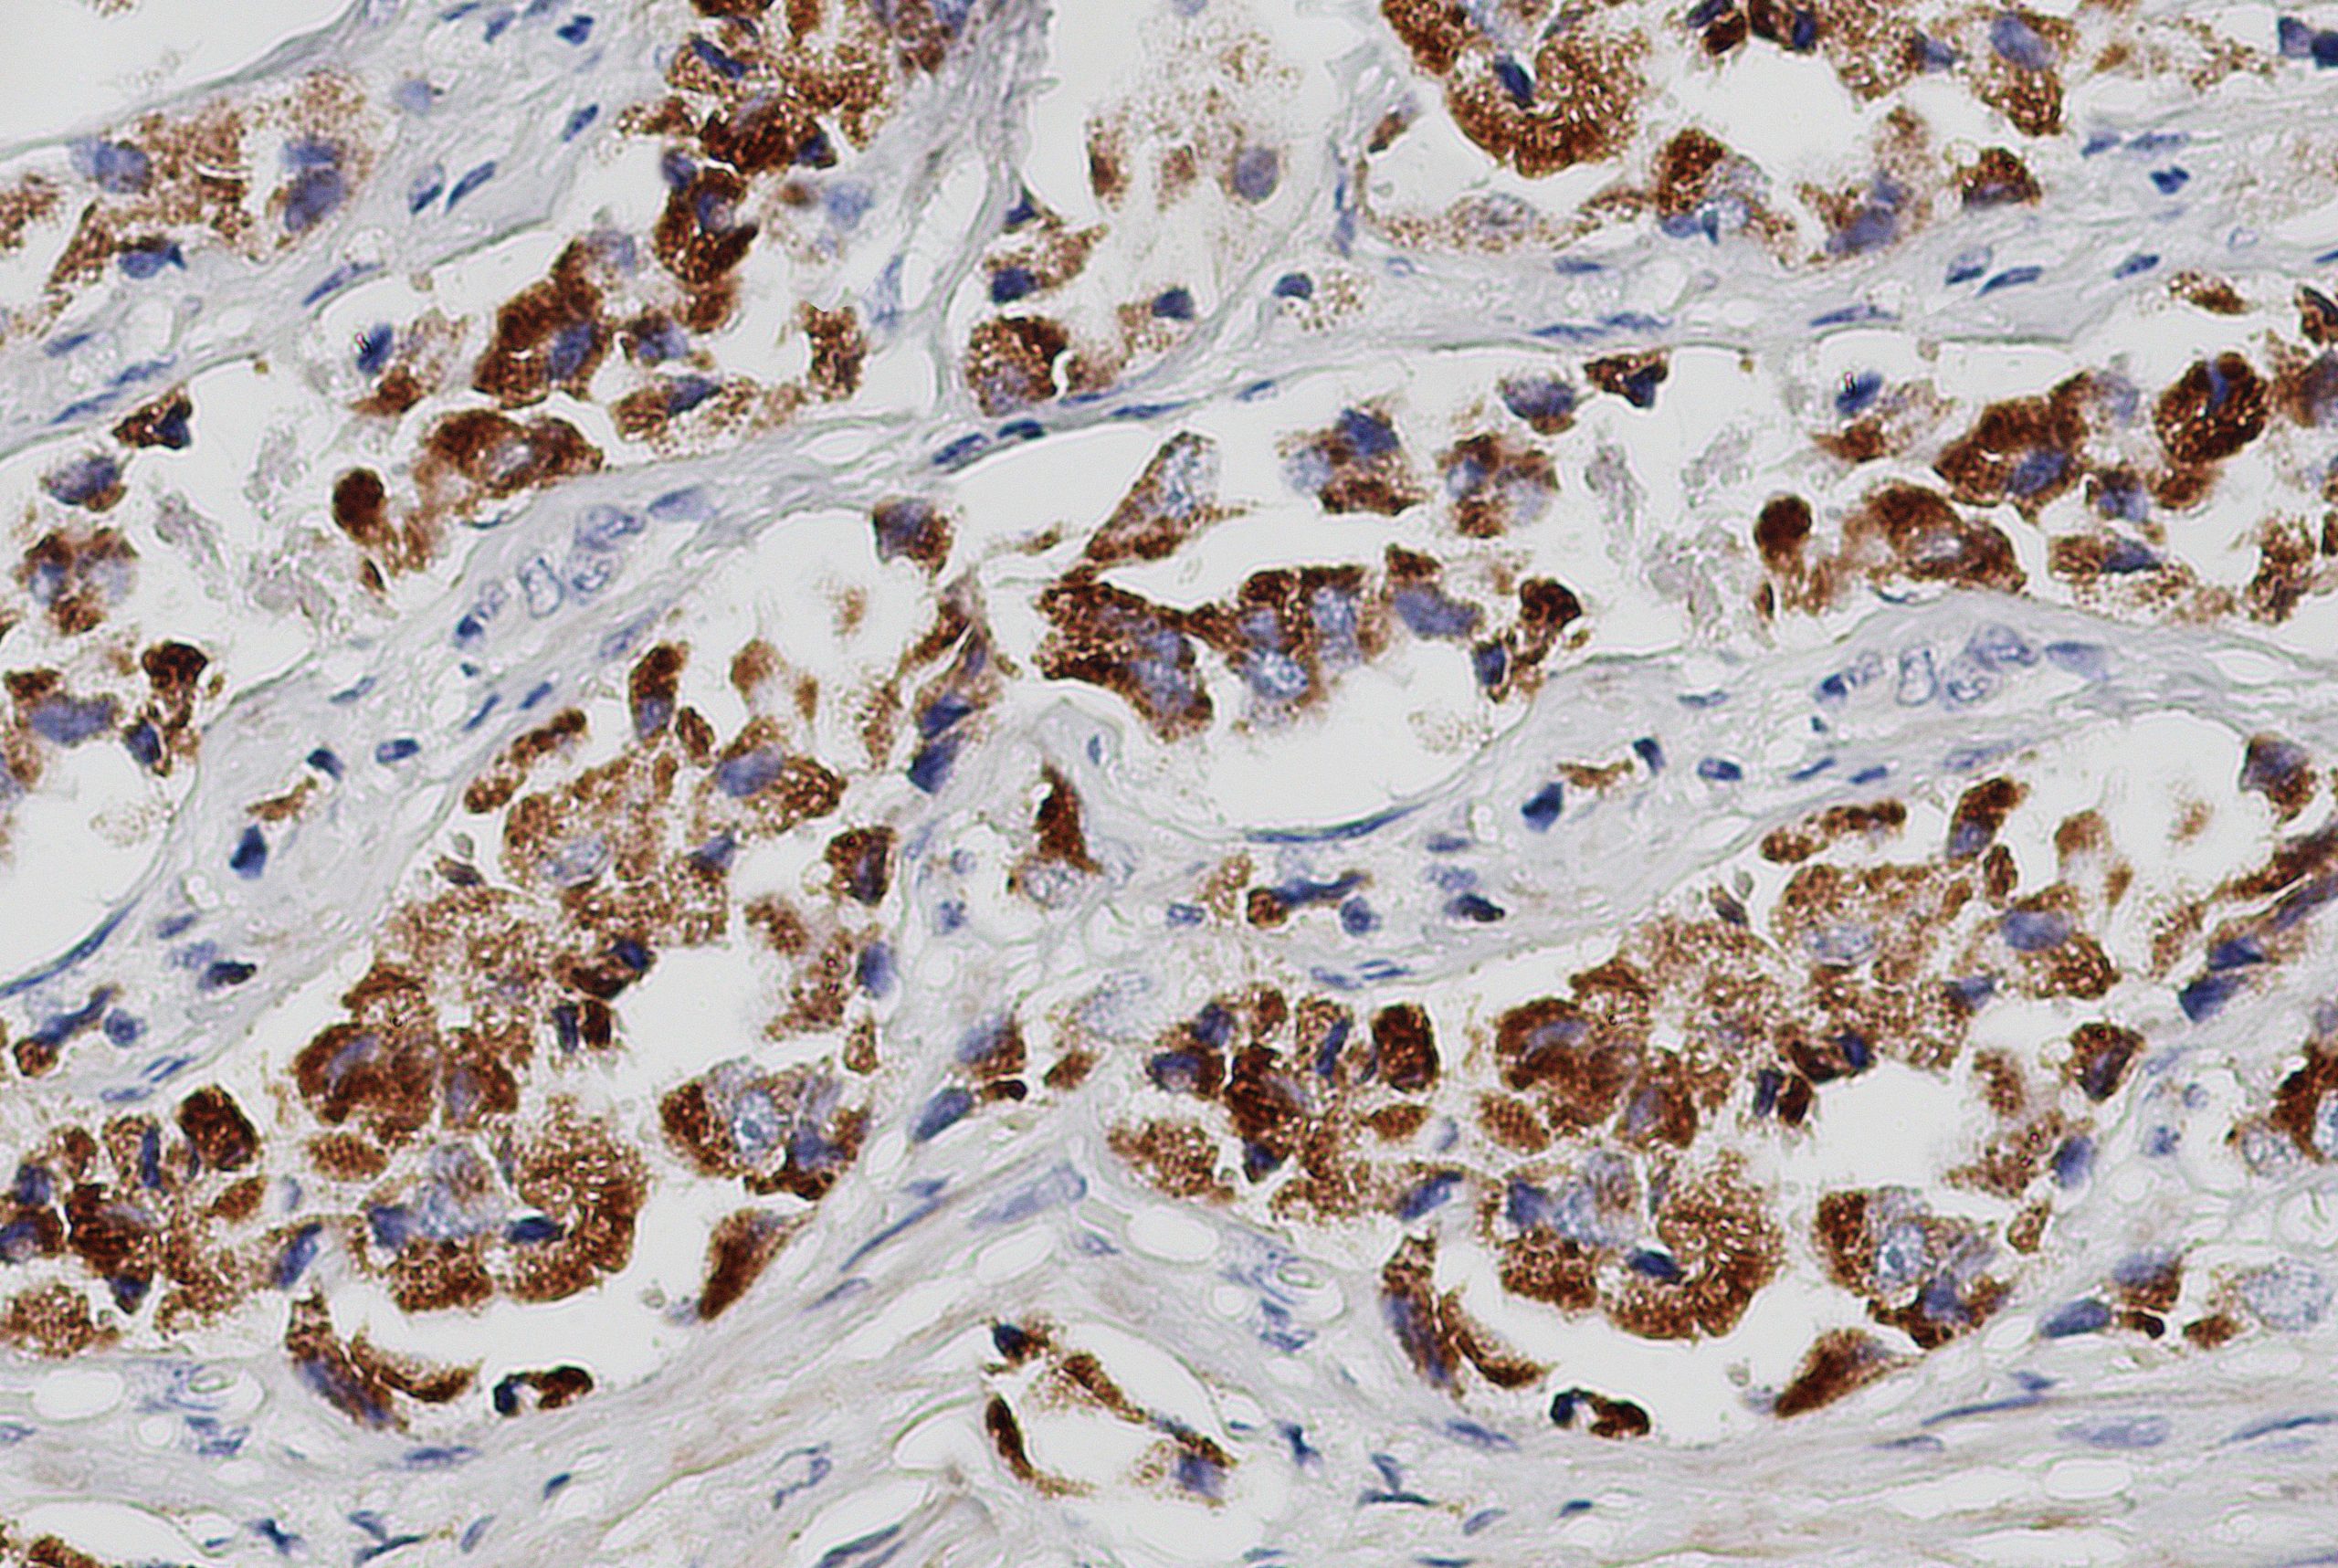

Anti-YAP

YAP encodes a nuclear effector of the Hippo signaling pathway which plays a pivotal role in regulating tissue growth and organ size. Deregulation of the Hippo pathway causes tumor formation and malignancy and hence, YAP may function as a potential target for cancer treatment. YAP is expressed at high levels in the lung, placenta, prostate, testis and ovary.

| Tissue Type/Cancer Type | Breast Carcinoma Tissue |